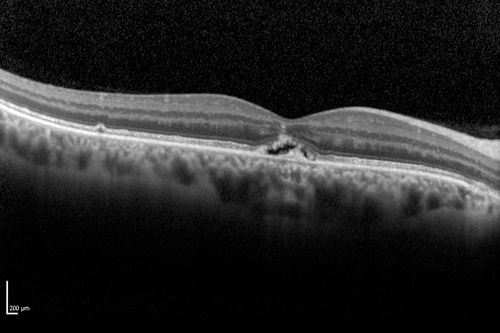

Best Disease - SD OCT Line Scan

Best Disease - 43 Year Old Woman